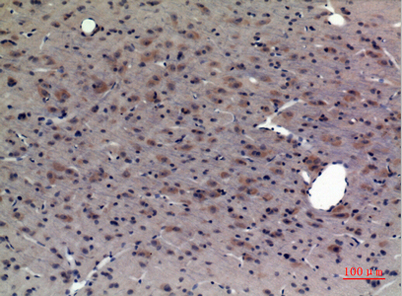

| Dilutions: | Western Blot: 1/500 - 1/2000. Immunohistochemistry: 1/100 - 1/300. Immunofluorescence: 1/200 - 1/1000. ELISA: 1/5000. Not yet tested in other applications. |